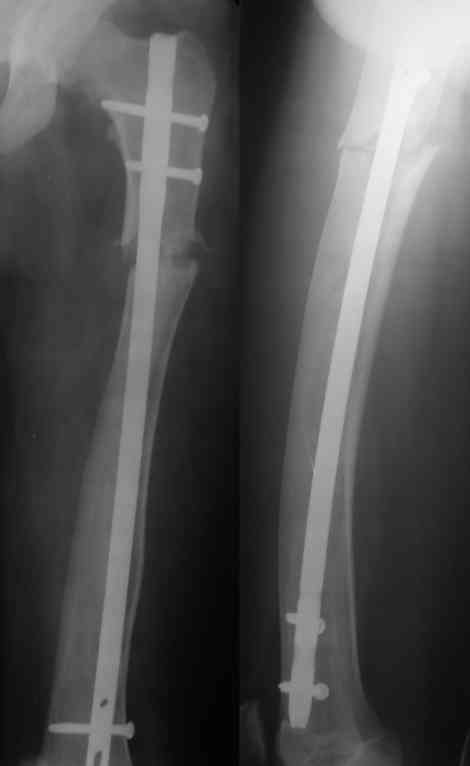

Поступила пациентка 20 лет с патологическим переломом бедра в С/З, находилась под наблюдением детских ортопедов по поводу незавершенного остеогенеза с рождения. За последний год перелом бедра был уже дважды, лечилась консервативно на вытяжении.На сегодняшний день имеется вот такая картина. Бедро деформировано на всем протяжении, остеопороз, участки остеосклероза. Уважаемые коллеги, какие будут соображения по тактике лечения. С уважением Леонид

Смущает искривленная ось бедра, и достаточно узкий костномозговой канал, конечно склонялись к закрытому блокирующему остеосинтезу, даже рассматривался вариант Fixation но к сожалению нет пока гибких сверел, а они в данном случае скорее всего понадобились бы. Скорее всего остановимся на пластине с угловой стабильностью (Рыбинск), подскажите если есть у кого опыт на сколько они( Рыбинские пластины) соответствуют заявленным свойствам.

На этих снимках не очень хорошо видно структуру кости на всем протяжении. Видимо, попытаться сформировать канал при наличии инструментов типа очень длинного шила, лучше нескольких, разных диаметров, можно было бы. Мы такие инструменты себе сделали сами.

Еще одна проблема - ось бедра не на всем протяжении будет совпадать с осью гвоздя. Хотя канал можно и кривой сформировать, гвоздь в него потом не ввести. Это более менее легко решается чрескожной остеотомией или несколькими, прямо по ходу введения гвоздя.

Закрыто заштифтовать не так просто - нужен серьезный опыт: помимо искривления оси бедра у таких больных обычно сужен косттномозговой канал, а сама кость в сечении саблевидная. Хотя механически это оптимально, но провести гвоздь достаточного диаметра для блокирования непросто. У нас была похожая пациентка весной - закончили пластиной. Снимки сейчас продемонстрировать не могу, но интересная фотография участка резецированной кости осталась - в приложении.